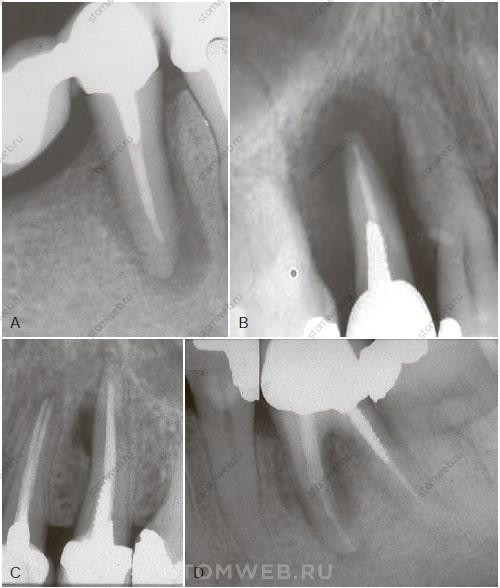

Ранние проявления

На ранней стадии вертикального перелома корня может появиться боль или дискомфорт с пораженной стороны зуба. В частности, чувствительность и дискомфорт могут появляться при жевании, боль чаще тупая, в противоположность острой боли, типичной при трещине бугра или зуба с живой пульпой. При прогрессировании поражения и сопутствующей инфекции часто возникает отечность и может появиться свищевой ход, локализованный более коронально, чем свищевой ход при хроническом апикальном абсцессе (Рис. 21-12). Все эти признаки затрудняют дифференциальную диагностику с отрицательной динамикой эндодонтического лечения. На ранних стадиях рентгенологические проявления редки, так как (1) пломбировочный материал в корневом канале загораживает трещину (Рис. 21-13, А), и (2) изображение корня накладывается на участок деструкции костной ткани (который все еще имеет небольшие размеры мезио-дистально)

РИС. 21-12 Свищевой ход расположенный коронально. А) Зуб 1.2 со свищевым ходом, локализованным на прикрепленной десне, что не характерно для хронического периапикального абсцесса. Верхние боковые резцы не попадают в зону риска вертикального перелома корня. В) Коронально расположенный свищевой ход от щечного вертикального перелома корня зуба 2.4. С) Свищевой ход в области маргинальной десны от зуба 4.6 с вертикальным переломом корня со щечной поверхности медиального корня.

РИС.21-13 Сравнение рентгенографии запломбированного и пустого каналов. А) Щечно-язычная проекция запломбированного канала с невозможностью обнаружения вертикального перелома корня на ранней стадии. В) Удаление пломбировочного материала из канала и снимки под различными углами могут помочь обнаружить вертикальный перелом корня.

РИС. 21-14 Сравнение рентгенографии очага деструкции кости в связи с вертикальным переломом корня на ранней и на поздней стадиях. На ранней стадии очаг деструкции кости (красный) вряд ли может быть обнаружен на прицельной рентгенограмме, поскольку перекрывается изображением корня (А,В). На более поздней стадии , когда очаг деструкции распространился до кортикальной пластинки (С), и выступает за пределы силуэта корня (С,D) выглядя при этом как участок просветления вдоль корня (D).